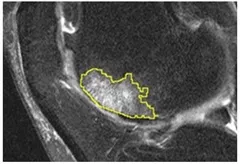

Bone Marrow Lesion (BML) Description:

We have a customized semiautomatic software to measure BMLs, which we defined as regions of high-signal intensity within bone on IW FS MR images (femur, tibia, and patella).

Bone marrow lesion

Driban JB, Price LL, Lo GH, Pang J, Hunter DJ, Miller E, Ward RJ, Eaton CB, Lynch JA, McAlindon TE. Evaluation of bone marrow lesion volume as a knee osteoarthritis biomarker - longitudinal relationships with pain and structural changes: data from the Osteoarthritis Initiative. Arthritis Res Ther. 2013;15(5):R112.

Zhang M, Driban JB, Price LL, Lo GH, McAlindon TE. Magnetic Resonance Image Sequence Influences the Relationship between Bone Marrow Lesions Volume and Pain: Data from the Osteoarthritis Initiative. BioMed research international. 2015;2015:731903.